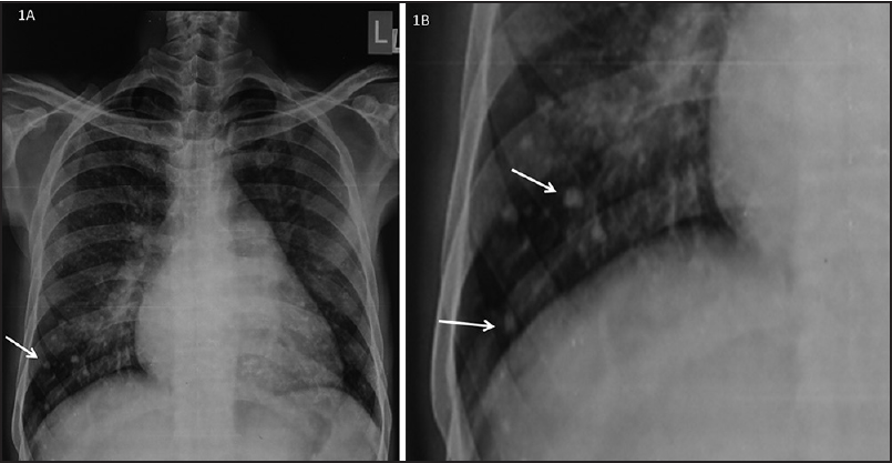

CXR Z

Left atrial enlargement

Evidence of mitral calcification

PA view: ⇒ Left atrial enlargement:

- Convexity or straightening of the left atrial appendage.

- Left heart border is straight or convex

- Double density of RTÂ cardiac border

- Elevation of the left main bronchus and splaying of the carina